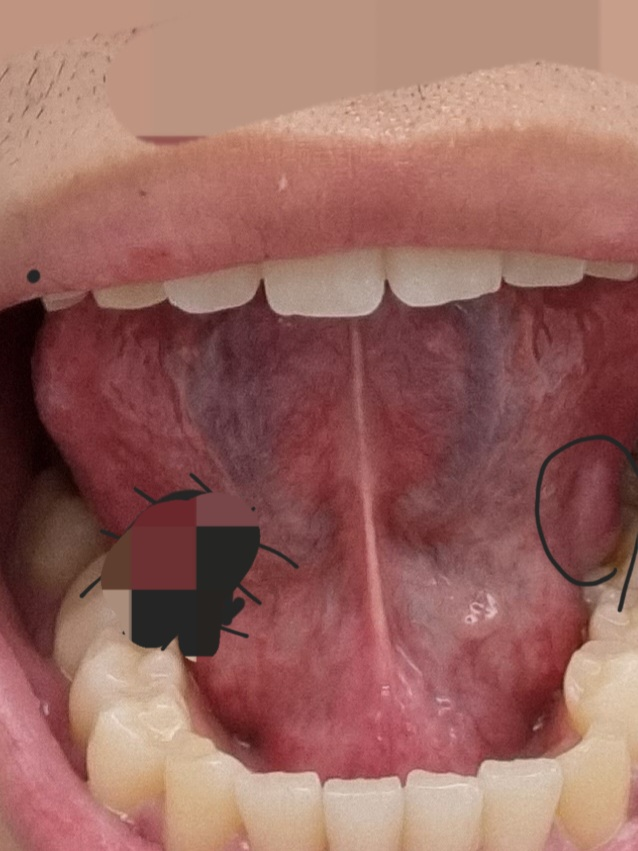

안녕하세요. 안상우 치과의사입니다.

혀 아래면에는 정맥이 지나가는 부위등이 튀어 나올수 있습니다.

병적인 증상은 아니기 때문에 너무 걱정을 하지 않으셔도 될것으로 생각되지만 해당부위에 불편감이 있다면 치과에서 진료를 받아 보는것이 좋습니다.